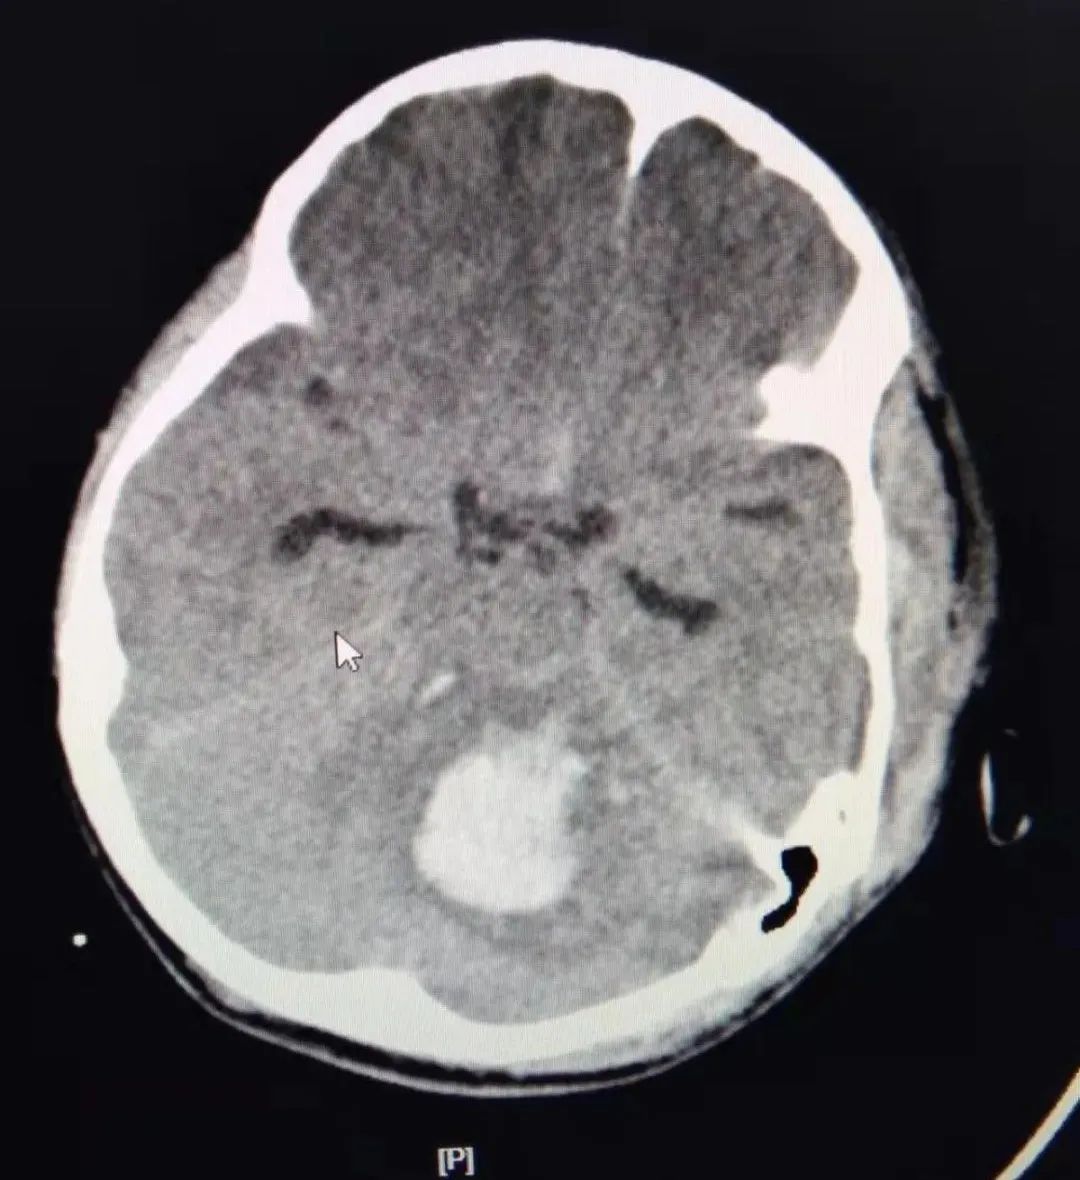

通过相关检查,初步诊断:其意识丧失、呼吸循环衰竭,处于休克状态。CT显示严重多发脑挫裂伤、小脑出血,合并严重脾破裂、重度肺挫伤,胸腔、腹腔大量积血,肾挫伤、骨盆骨折。病情十分严重,生命危在旦夕!

术后发现由于小脑外伤性血肿进行性增多已达20毫升,严重脑水肿,脑干受压,随时有枕骨大孔疝发生和呼吸、心跳骤停的致命危险!

神外NSICU张国庆团队立即接棒进行微创手术清除脑内血肿,手术历经1小时后顺利完成。